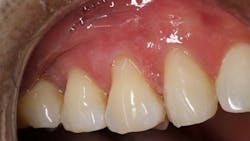

A 45-year-old male presented for three class V fillings. Teeth nos. 4 and 5 had cervical abrasions (or erosion), and no. 6 had a defective existing composite fillingThe teeth to be restored in this case had excellent gingival health, and the patient was in good health. The patient was anesthetized with one carpule (1.7 ml) of lidocaine with 1:100,000 epinephrine.